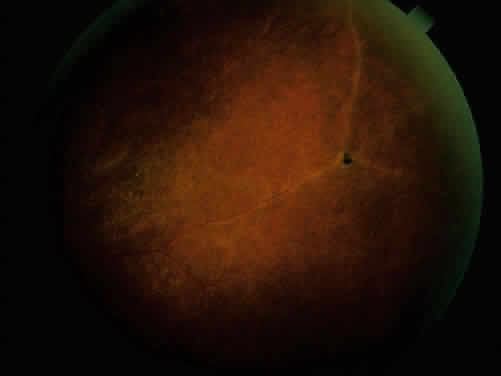

Ocular inflammatory changes include conjunctivitis, episcleritis, keratitis, acute and chronic iridocyclitis, and posterior changes as well.38–43 The acute iridocyclitis is milder and frequently not accompanied by as much pain, photophobia, and redness as in the acute iridocyclitis associated with other spondyloarthropathies. Mild injection of the conjunctival and episcleral vessels and blurred vision may be the only symptoms of an acute flare of activity. The endothelium of the cornea usually has cellular debris and poorly formed keratic precipitates in the lower cornea. The anterior chamber contains cells and moderate flare, and a protein clot is not infrequent in the pupil, with early formation of posterior synechiae (Fig. 6); however, the synechiae are usually more easily broken than in ankylosing spondylitis and Reiter's syndrome.44 Treatment with topical corticosteroids and mydriatics is usually effective. The activity of the iridocyclitis has been reported to follow the activity course of the inflammatory bowel disease. Systemic treatment of inflammatory bowel disease has been noted to help the ocular inflammation. Decreasing the systemic treatment occasionally allows ocular inflammation to become visible and requires close observation and appropriate increase in local therapy.39,44–46 Surgical resection of inflamed bowel for other medical reasons has sometimes been reported to coincide with lessening of ocular inflammation,44,46 but these observations need better evaluation.42 Posterior segment manifestations, including retinal and choroidal vascular disease, are also sometimes noted.47,48

Fig. 6. Partial posterior synechiae and fibrin clot in pupil with iridocyclitis and Crohn's disease.